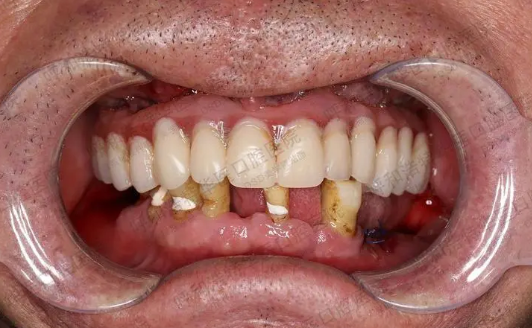

往后,我们也基本忽略了爷爷的“倔强”,硬是把他带到了我们知道的一家口碑不错的牙科检查看下,当然老人家只是比较心疼钱来之不易,不舍得我们把在他身上过多花费,我们当然也明白,所以就带着爷爷去了。医生检查完以后发现爷爷的牙齿大部分都已经松动,牙周病的程度时比较严重了,但是一开始没有重视问题也没有及时治疗,所以好几颗牙齿都保不住了。

因为原先是可以治疗的,但是有些牙齿因为缺了以后,旁边的牙少了一边的支撑,就出现了现在这种情况,这样下去不管不顾牙齿情况会越来越差,就不单单是外貌会受到影响,就连咀嚼功能和消化功能都会收到影响。

经过我们一家人讨论,也是听了爸爸的建议,宁愿多花一点钱也不能让爷爷以后在牙齿上再出什么大问题。于是我们就选了做种植牙的方案,但是因为爷爷原先牙周就有问题,先把牙周问题治疗好了以后,才做种植牙。

种牙当天的时候,爷爷实现种上了牙根,原先我们还是会担心很疼,差不多3个小时左右后,我们悬着的心就放下来了,爷爷说除了打了麻药还有点发麻,其他没啥感觉,麻药过了以后因为有服用止痛药,所以都很顺利。